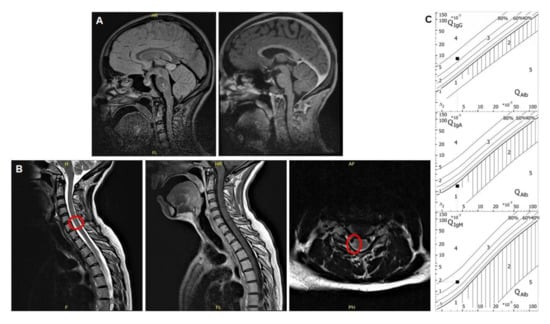

:1. Case Report